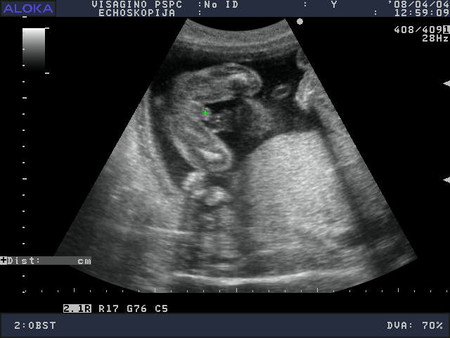

Vsem privet!Vhera bilaa na pervom uzi...vpehatlenij mnogo!Hto tam vitvoriaet rebenohek!!!Kuvirkaetsia i ruhki,nozki potiagivaet....prelest.Srok podtverdili 12 nedel i data rodov 08.08.2008

Nu a tam budet vidno.Skazali serdcebienie serjoznoe,poxoze tretij malhishka,nu da ne budem zagliadivat vpered.Ostavim eto na potom....v 20 nedelek pojdem posmotrim